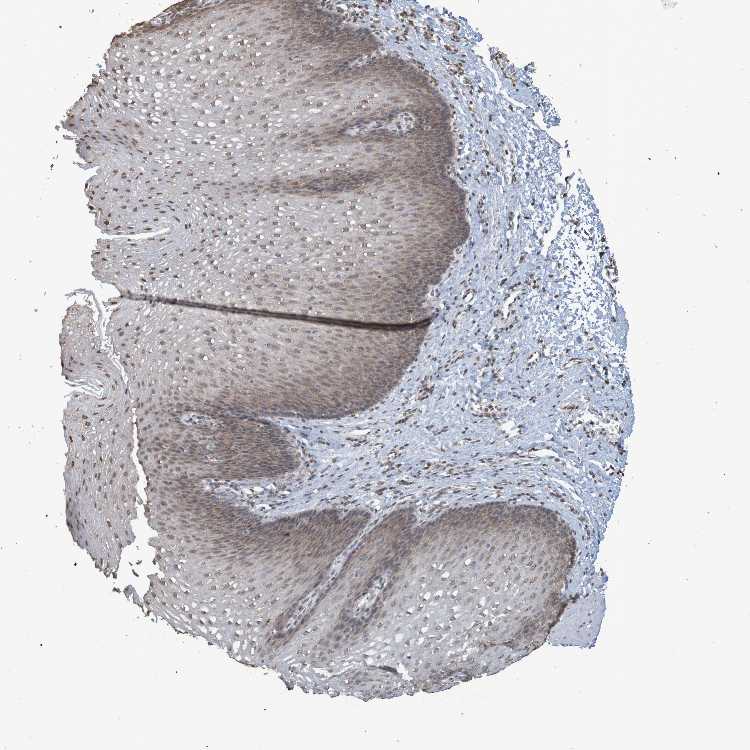

ESOPHAGUS - Antibody stainingi

Antibody staining in the annotated cell types in the current human tissue is reported as not detected, low, medium, or high, based on conventional immunohistochemistry profiling in selected tissues. This score is based on the combination of the staining intensity and fraction of stained cells.

Each image is clickable and will lead to virtual microscopy that enables deeper exploration of all samples and also displays staining intensity scores, fraction scores and subcellular localization as well as patient and tissue information for each sample.

Antibody CAB011197

Squamous epithelial cells Medium